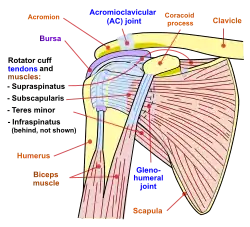

| Diagram of the human shoulder joint | |

The shoulder joint is composed of three bones: the clavicle (collarbone), the scapula (shoulder blade), and the humerus (upper arm bone) (see diagram). Two joints facilitate shoulder movement. The acromioclavicular (AC) joint is located between the acromion (part of the scapula that forms the highest point of the shoulder) and the clavicle. The glenohumeral joint, to which the term "shoulder joint" commonly refers, is a ball-and-socket joint that allows the arm to rotate in a circular fashion or to hinge out and up away from the body. The "ball" is the top, rounded portion of the upper arm bone or humerus; the "socket," or glenoid, is a dish-shaped part of the outer edge of the scapula into which the ball fits. Arm movement is further facilitated by the ability of the scapula itself to slide along the rib cage. The capsule is a soft tissue envelope that encircles the glenohumeral joint. It is lined by a thin, smooth synovial membrane.

The bones of the shoulder are held in place by muscles, tendons, and ligaments. Tendons are tough cords of tissue that attach the shoulder muscles to bone and assist the muscles in moving the shoulder. Ligaments attach shoulder bones to each other, providing stability. For example, the front of the joint capsule is anchored by three glenohumeral ligaments.

The rotator cuff is a structure composed of tendons that, with associated muscles, holds the ball at the top of the humerus in the glenoid socket and provides mobility and strength to the shoulder joint.[2]

Four filmy sac-like structures called bursa permit smooth gliding between bone, muscle, and tendon. They cushion and protect the rotator cuff from the bony arch of the acromion.